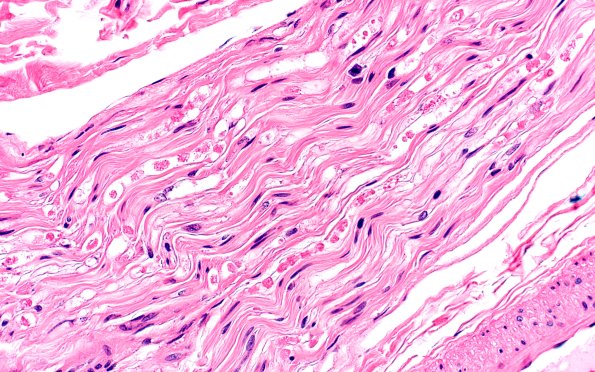

9A4 Axonal Degeneration, fulminant (Case 9) H&E 4

Extensive axonal degeneration is shown. (H&E)